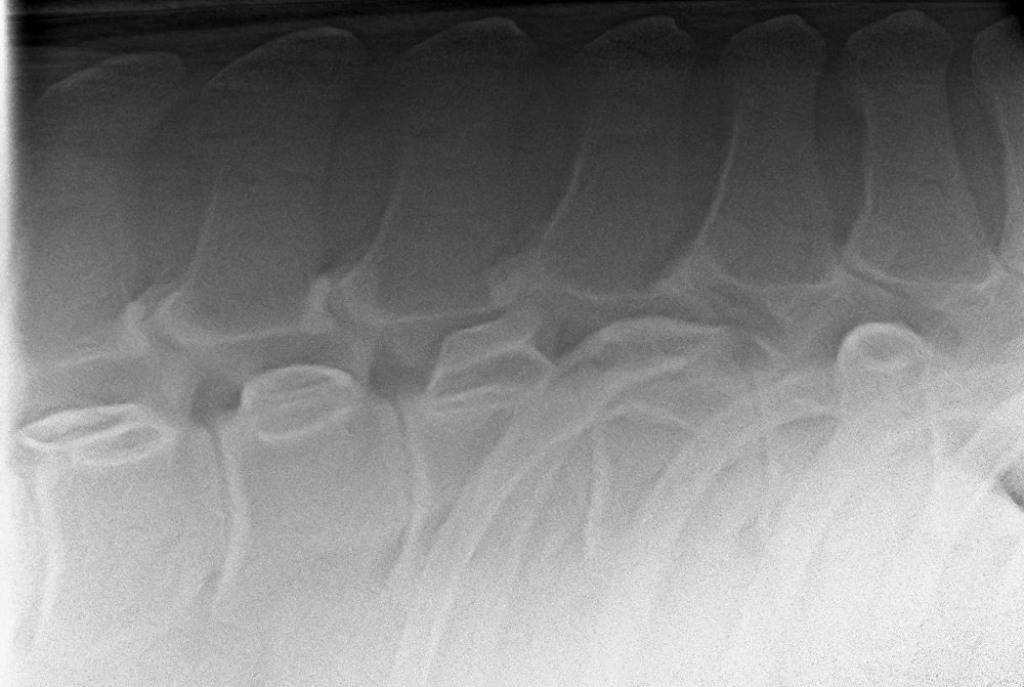

Röntgenfoto van een ernstige vorm van kissing spines en spondylose (versmelting van de wervels)

Foto: Röntgenfoto van een ernstige vorm van kissing spines en spondylose (versmelting van de wervels)

Kissing spines is een beladen term en een gevreesde aandoeningen bij paarden. Bij kissing spines komen de doornuitsteeksels van de ruggenwervels dichter bij elkaar te staan of komen zelfs tegen elkaar aan. Dit kan leiden tot irritatie van het bot van de doornuitsteeksels en daardoor veranderingen van de vorm van de doornuitsteeksels en het bot van de spinaaluitsteeksels zelf. Ook spelen veranderingen bij de aanhechtingen van de spinaalligamenten een rol in dit probleem. Niet alle veranderingen van de doornuitsteeksels zijn echter pijnlijk of een reden voor (rug)klachten. Belangrijk is om verschil te maken tussen de röntgenologische diagnose kissing spines en de klinische diagnose (oorzaak van pijn of probleem). Daarom is de diagnose van kissing spines niet altijd even eenvoudig te stellen. Meestal is een uitgebreid klinisch onderzoek aangevuld met beeldvorming van de wervelkolom noodzakelijk om een correct diagnose te stellen en andere oorzaken uit te sluiten.